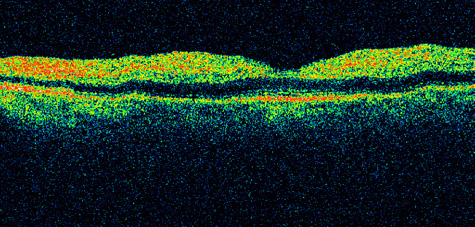

Hypoperfusion retinopathy is characterized by dot and blot hemorrhages in the midperiphery of the fundus, by venous tortuosity and engorgement, by microaneurysms, and by the occasional sludging of blood within the veins. Fluorescein angiography may show areas of capillary nonperfusion; it may also show microaneurysms in the midperiphery and slow arm to retina or arteriovenous transit time (Fig. 9A and 9B).174 The condition does not usually affect the posterior pole, and patients typically have normal visual acuity, although an occasional patient may have macular edema.174 The entire periphery of the eye is usually affected, although there may be more hemorrhages in one quadrant than another. Patients occasionally experience ocular discomfort or eye pain despite normal intraocular pressure. Reduction of the ophthalmic arterial pressure is a pathognomonic feature. Disc edema and disc collaterals are generally not present. The electroretinogram shows abnormalities in both the a- and b-waves (see Fig. 9C).

Fig. 9. Intravenous fluorescein angiogram of a patient with hypotensive or hypoperfusion retinopathy. A: There is a marked delay in the choroidal and retinal filling. B: In the recirculation of the angiogram, there is a characteristic staining of both arteries and veins. C: Electroretinogram shows normal a- and b-waves in the normal right eye (upper tracing) and marked redirection of the a- and b-waves in the affected left eye (lower tracing).